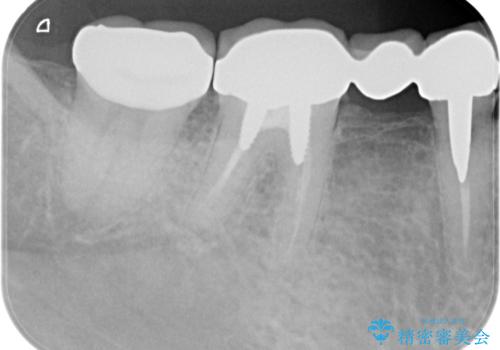

割れたセラミック下に再発した虫歯

- 「以前治療したセラミックが割れ、黒くなっているので診てほしい。」と希望され来院されました。

割れてしまったセラミックインレーの下には大きな虫歯の再発が認められました。

神経を温存するよう、丁寧に虫歯を除去したのち、オールセラミックジルコニアクラウンによる機能回復を行いました。

虫歯は放置すると大きくなり、神経に達していた可能性が高いと思われました。

今回は神経を温存し治療を行うことができました。